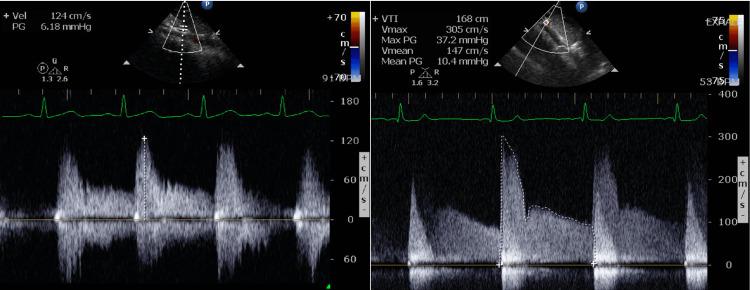

Between 2013 and 2020, there were 82 children, 55 females (67%), mean age 13.9 ± 3.2 years, with MALS and complete record. Mean velocity across the stenotic area was 2.6 ± 0.4 m/s. Forty-six patients (57%) had abdominal pain. Age, gender, weight, body mass index (BMI), and Doppler velocity had no statistically significant influence on symptom occurrence. Conversely, patients with joint hypermobility and symptoms of orthostatic intolerance were more likely to have abdominal pain from MALS. Of 24 patients with joint hypermobility, 18 patients had abdominal pain (p=0.027). Thirty-eight patients with orthostatic intolerance (OI) with MALS complained of abdominal pain vs 13 patients with OI and no abdominal pain (p=<0.0001).

2013年至2020年期间,有82名儿童被诊断为MALS且记录完整,其中55名女性(67%),平均年龄13.9±3.2岁。狭窄区域的平均流速为2.6±0.4米/秒。46名患者(57%)有腹痛症状。年龄、性别、体重、体重指数(BMI)和多普勒流速对症状发生没有统计学上的显著影响。相反,关节活动过度和体位性不耐受症状的患者更有可能因MALS而出现腹痛。在24名关节活动过度的患者中,18名患者有腹痛(p=0.027)。38名患有MALS的体位性不耐受(OI)患者主诉腹痛,而13名患有OI但无腹痛的患者(p<0.0001)。